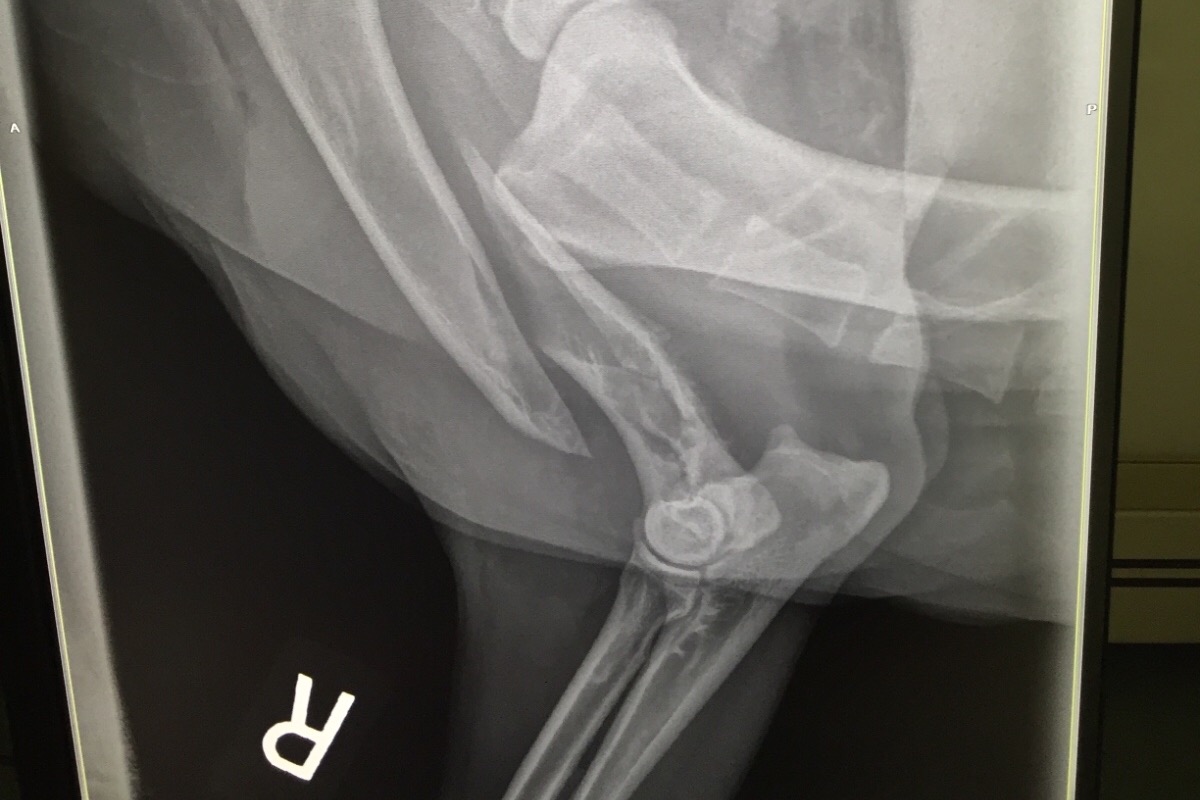

Meet Sadie, our beloved 11 year old American Foxhound. Sadie (also known as Sadie Lady) is 90 pounds of pure love. She brings our family and all of those who know her so much joy. We often say that she could have been a therapy dog. She is remarkably empathetic. She shares in your happiness when times are good, and she gives you extra snuggles when times are tough. On Friday, July 13th, Sadie fractured her right arm while out on a walk at the beach. We later found out that she had fractured through a weakened area of bone caused by a large tumor in her humerus. She was admitted to the vet hospital where she was diagnosed with osteosarcoma, a bone cancer. As you can imagine, our family was crushed. The only way to save her life was surgery. Luckily for Sadie, and for us, her cancer was localized without metastasis to the chest or abdomen. Unfortunately, repairing the broken bone was not an option.